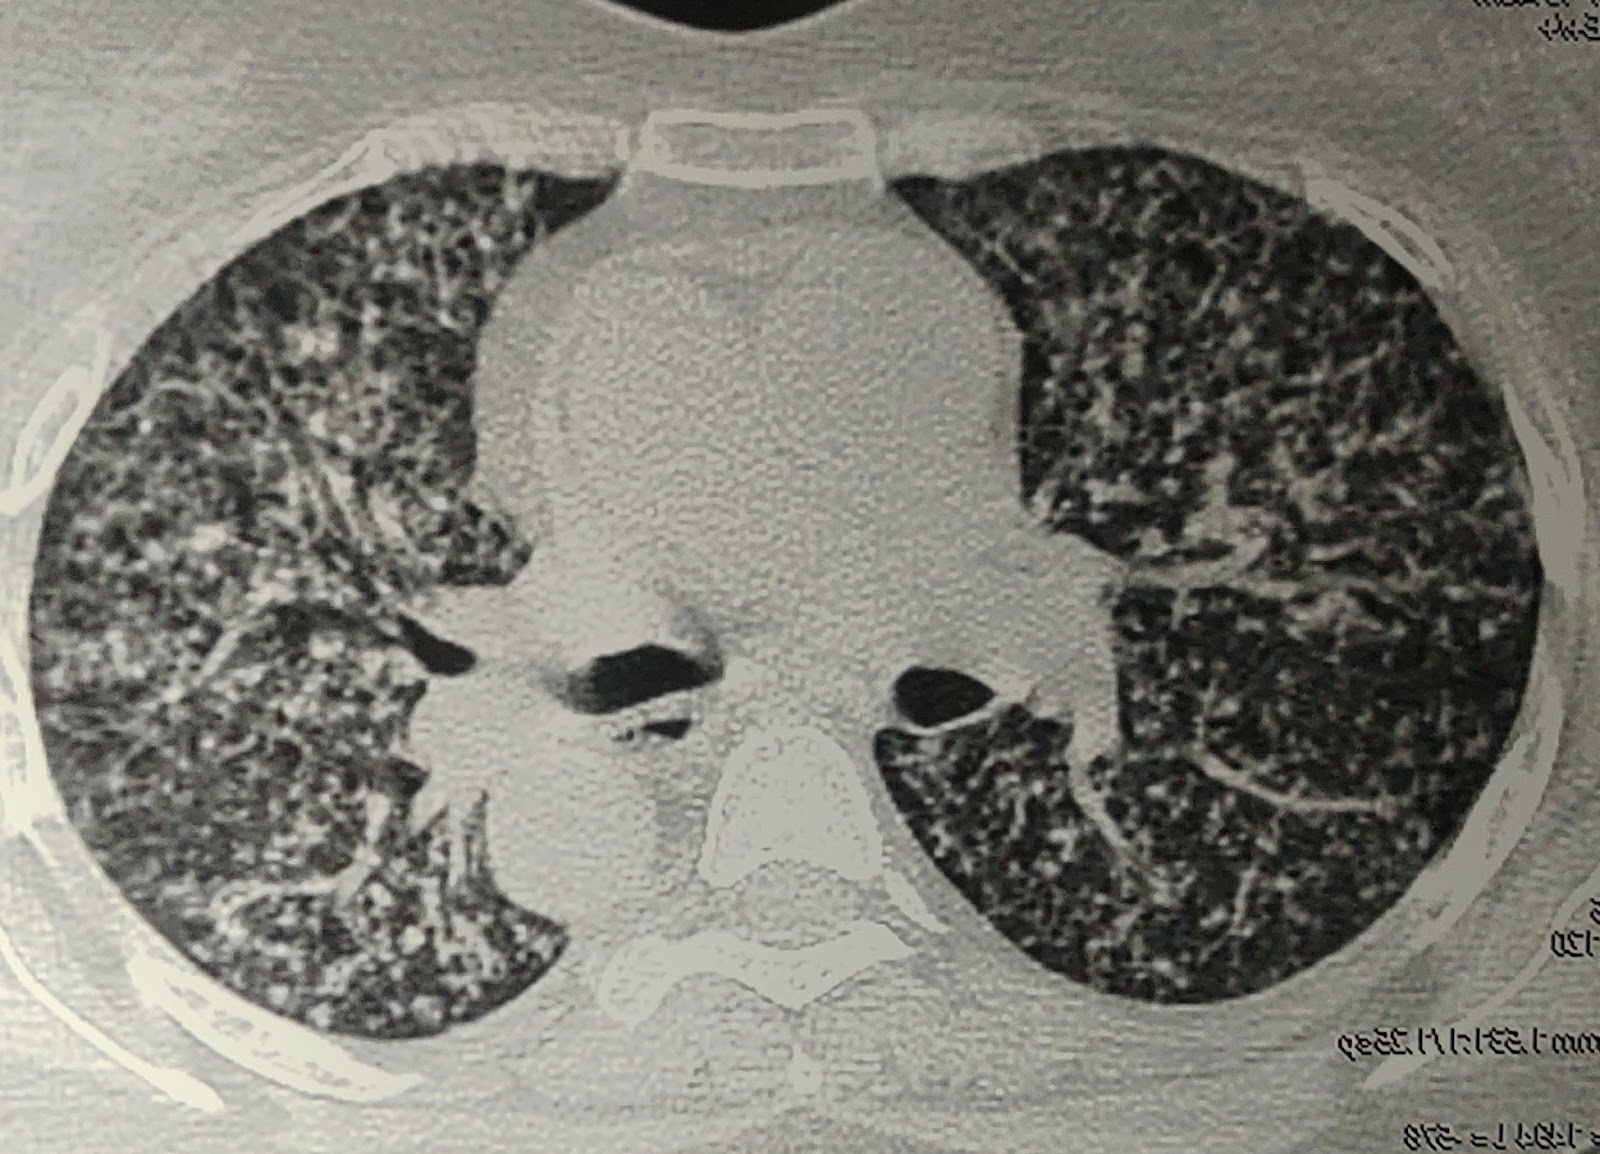

2 months back Pt had C/o cough with expectoration, pain in chest region. was diagnosed as PULMONARY MILIARY TB based on Chest X Ray and started on ATT. After 1 month of use she started developing redness and itching all over the body ATT induced Erythroderma, stopped ATT on 1 Feb 2022 for 20 days.

- Chest X-Ray